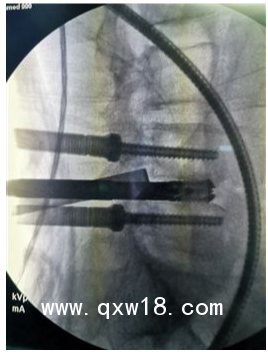

產(chǎn)品名:UBE 進(jìn)口雙通道手術(shù)醫(yī)療器械

企業(yè)名:山東奧蘇本醫(yī)療設(shè)備有限公司

最新UBE 進(jìn)口雙通道手術(shù)醫(yī)療器械招商